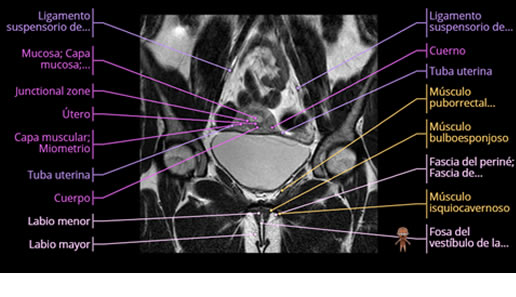

Se realizan adquisiciones en diferentes planos, con secuencias Spin echo y GRE, ponderadas a T1 y a T2, se utilizan pulsos de saturación de grasa y se administra medio de contraste a base de gadolinio.

El útero está en retroversión, retroflexión, y en posición central, se observa liquido en la cavidad endometrial, debido a la presencia de un Ca endometrial; en el anexo derecho se observa una masa quística que mide 3.8 x 2.2 cm de diámetro, corresponde a un quiste bilobulado, posee pared gruesa con componente solido puede tratarse de un Cistoadenocarcinoma, el cual realza con el medio de contraste de forma importante, entra dentro de una clasificación O-Rad tipo IV compatible con un Cistoadenocarcinoma